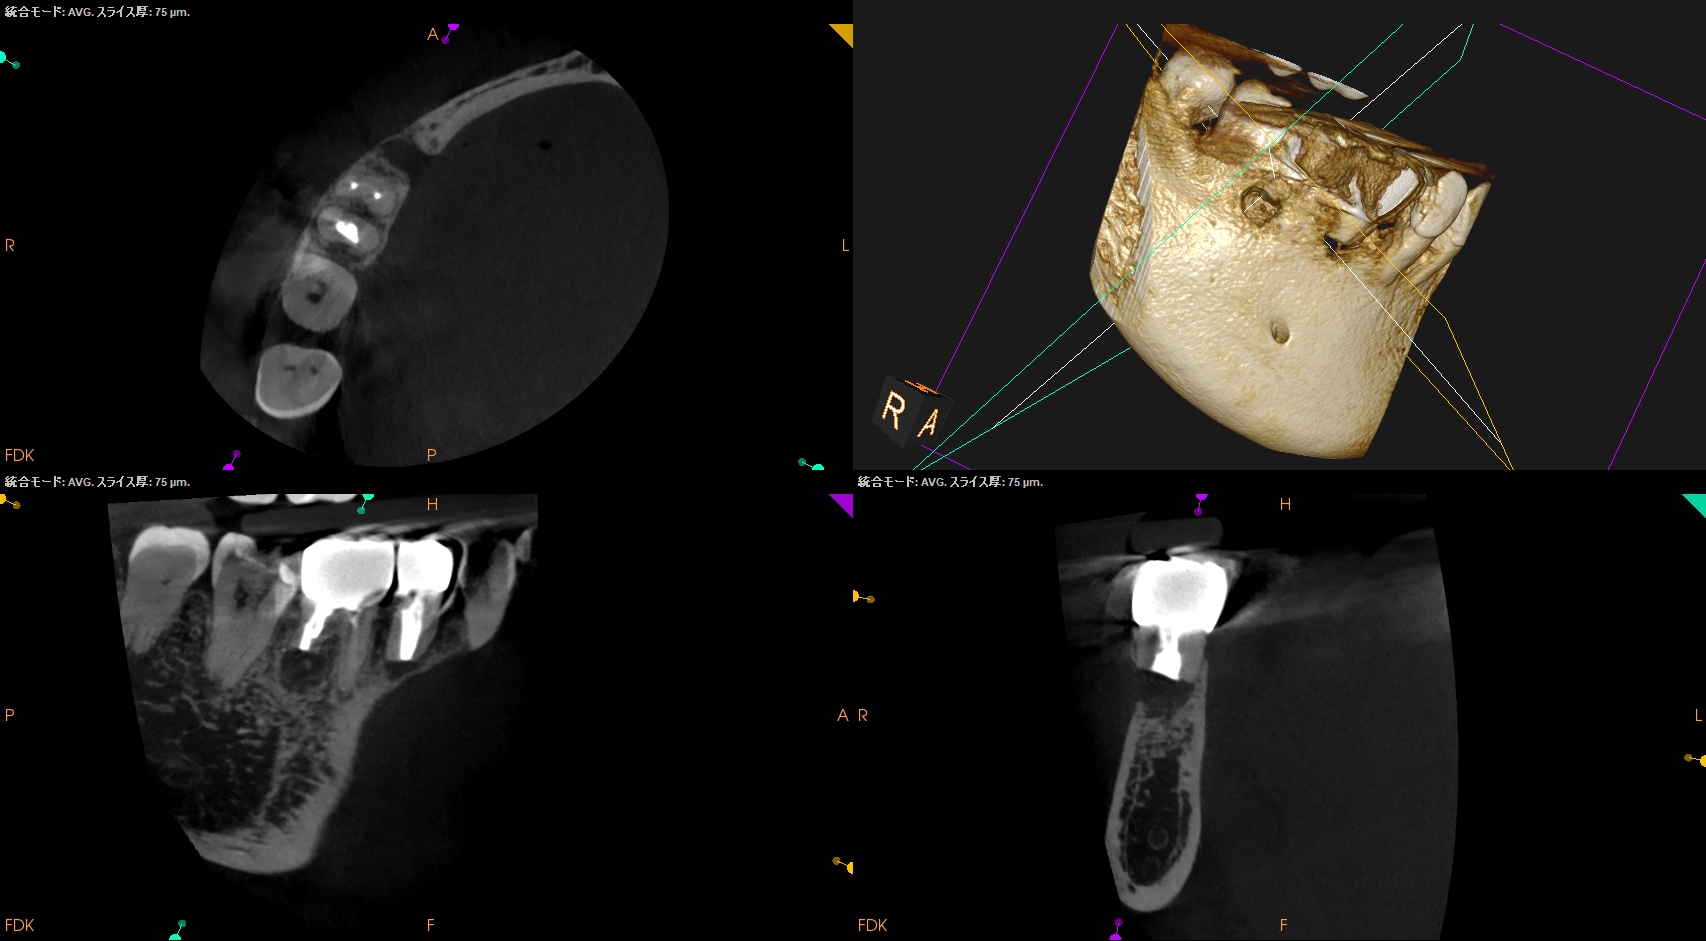

PA, CBCTを撮影した。

問題はないだろう。